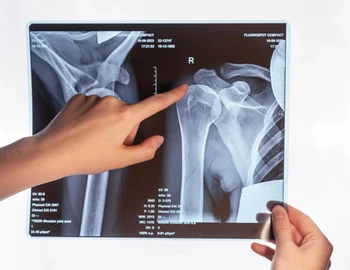

تمرینات تحمل وزن شانه بعد از آسیب دیدگی شانه یا جراحی، ممکن است برای رسیدن به بهبودی کامل لازم باشد. در طی برنامه توانبخشی تان، همراهی یک فیزیوتراپیست می تواند شما را از انجام صحیح تمرینات شانه و تحمل...